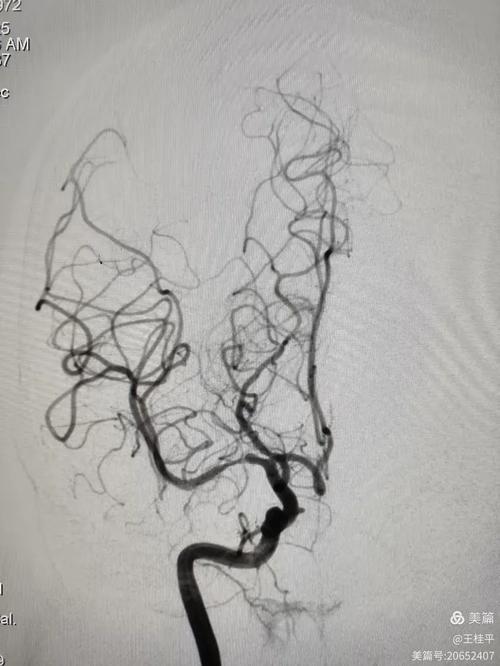

- DSA(数字减影血管造影):是诊断血管狭窄的“金标准”,但有创性,通常不作为常规复查手段,多在考虑介入治疗时使用。